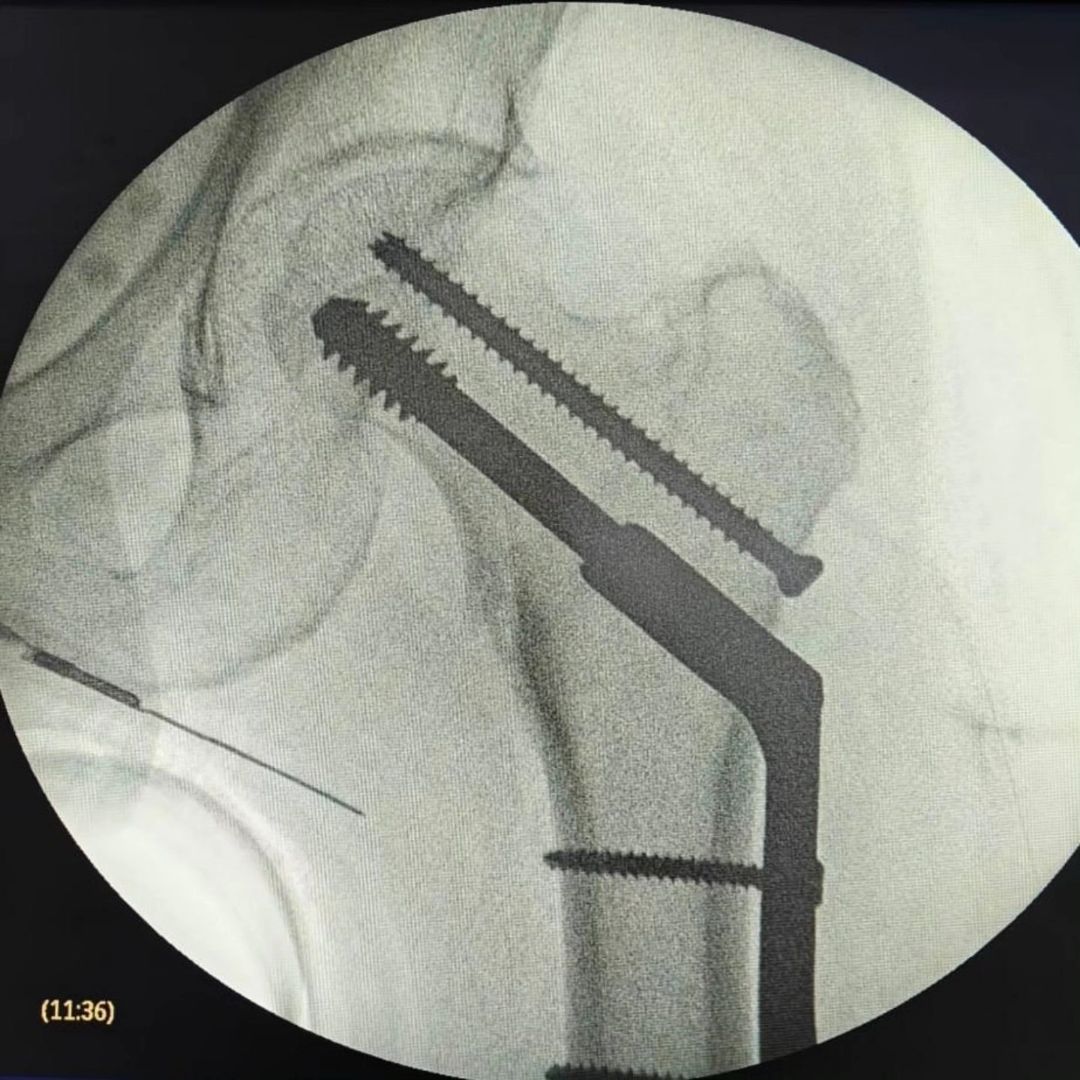

Mis habilidades más fuertes son el manejo de padecimientos de rodilla, cadera y hombro, así como procedimientos quirúrgicos asociadas a enfermedades degenerativas, fracturas y luxaciones.

• Artroplastia de la cadera con prótesis total

Muy agradecida con las finas atenciones del Dr. Ramirez, resolvio oportunamente la fractura de mi mama, con insumos de primera calidad y gran sentido humano , se los recomiendo al mil.

• Consultorio 2 "Clínica San Alejandro" Inmovilización de fracturas y/o luxaciones de cadera, fémur y rodilla  •